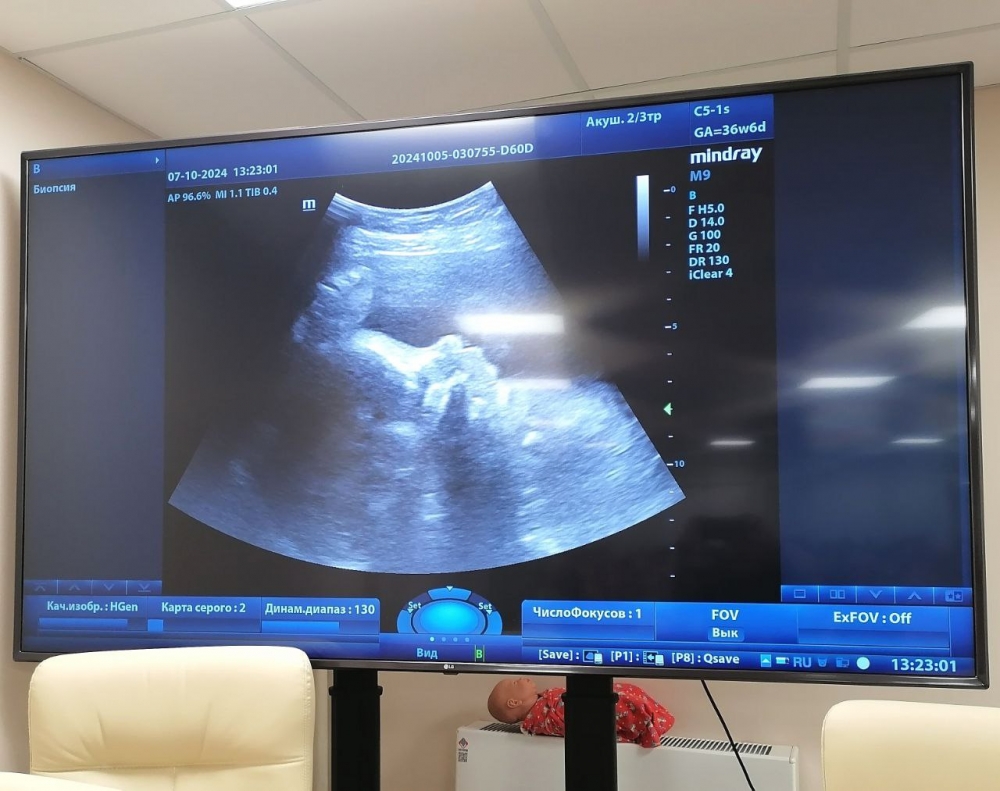

Впервые во время Дня беременных в центре состоялась акция «Два сердца» — во время которой будущие мамы-добровольцы открыто проходили недиагностическое исследование на передвижном аппарате УЗИ, слушали стук сердца своего малыша, делились эмоциями и впечатлениями. Акцию провели врачи Юлия Орлова и Кирилл Паулин.

фото: ТГ Перинатальный центр Йошкар-Олы